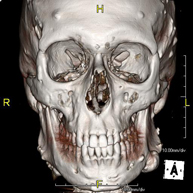

- Facial mass CT

Radiological test that provides high definition anatomical images of the facial mass (face) using CT (Computed Tomography) equipment. Indicated for: tumours, plastic surgery.